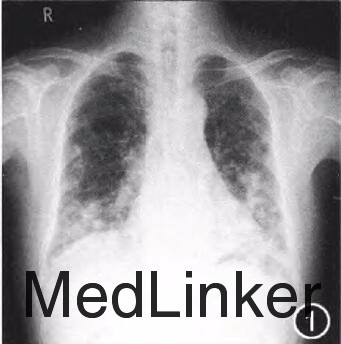

查体:未查见特殊 辅查:单核细胞百分比0.15(参考值0.03~0.13),c反应蛋白13.9mg/L(参考值<7.9mg/L),甲胎蛋白、癌胚抗原、CAl25、CAl99、CA153阴性,真菌-D-葡聚糖:97ng/L(参考值<80ng/L),曲霉菌半乳甘露聚糖0.19(参考值<0.50),自身抗体谱:抗内皮细胞抗体(+),抗核抗体、抗ENA抗体、抗线粒体抗体阴性。胸片示(图1):双肺野弥漫多发团片状、结节状高密度影,边界不清,双下肺为著。胸部CT提示(图2,3):双肺野弥漫多发团片状、结节状及索条状高密度影,大部分边界不清,以双下肺为著,部分结节内可见小空泡;纵隔多发大小不等淋巴结影,较大者约2.3cm×l.3cm。行肺内结节穿刺活检,病理检查:镜下见肺组织纤维化,淋巴、浆细胞浸润,可见多核巨细胞及坏死,符合肉芽肿性炎症性病变(图4)。免疫组织化学染色结果:PAS染色(-),抗酸染色(-)。活检组织块真菌培养阳性,六胺银染色检见孢子,病理见大量化生的纤毛柱状上皮细胞、大量炎细胞及坏死碎屑,未见恶性肿瘤细胞。